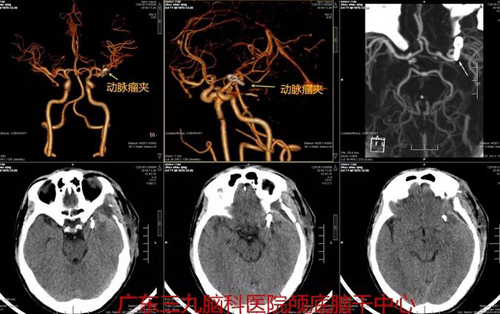

图1:术前CTA结果示左侧大脑中动脉瘤M1段分叉部动脉瘤

图3:术后CTA示左侧大脑中动脉瘤夹闭术后改变,未见瘤腔显示,其近远端血管通畅、未见明显减少